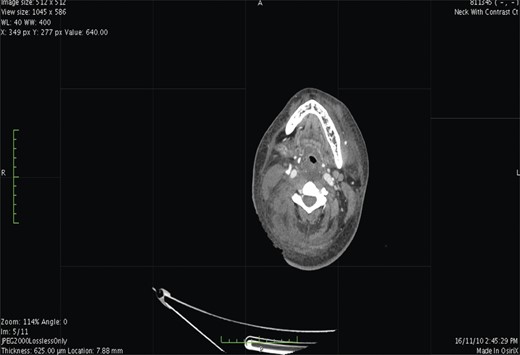

Contrast-enhanced computed tomography (CT) scan showed extensive cellulitis and thrombosis of the internal jugular vein and marked necrosis of the underlying muscles (Figs 1 and 2). The basic investigations revealed a haemoglobin level of 7.5 g/dl, a random plasma glucose level of 227 mg/dl and the fasting glucose level was 240 mg/dl.

Contrast-enhanced CT. At level of the mediastinum shows extensive inflammation involving the fat and the muscles on the right side.